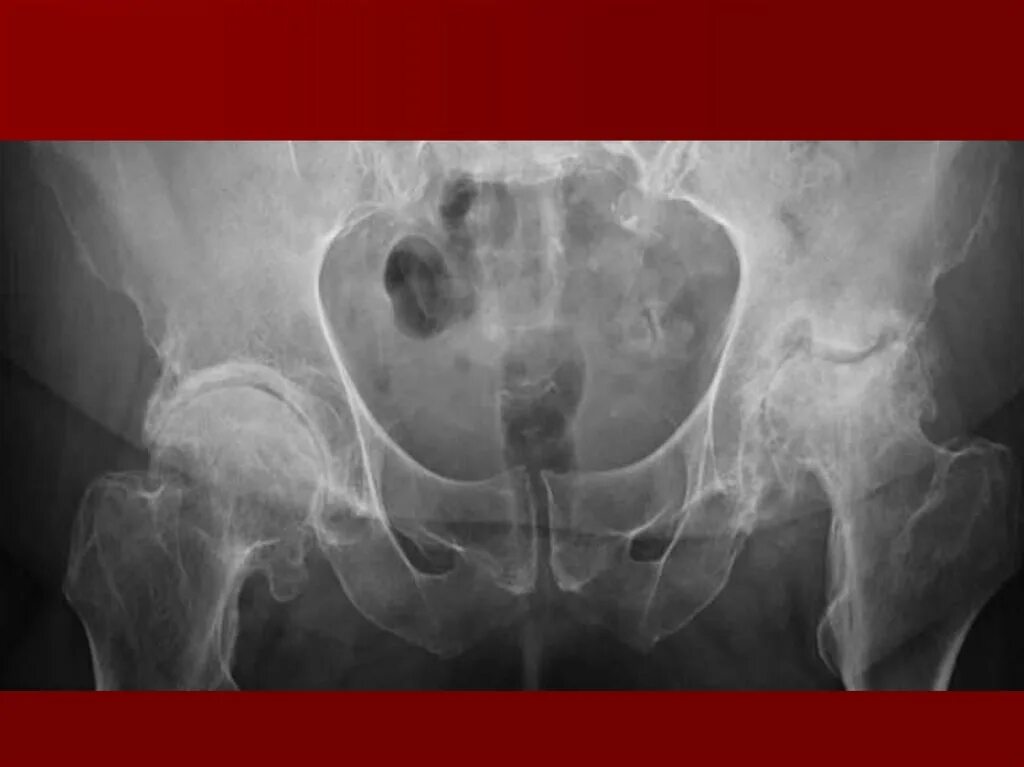

Доа тазобедренных суставов 1 степени что это